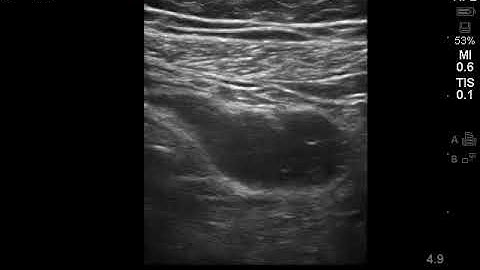

Appendicular perforation